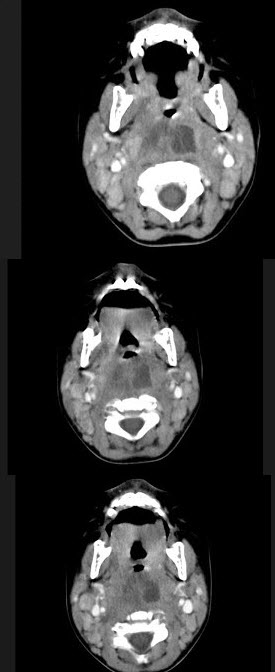

- 多项选择题10个月大的婴儿,发热,曾患中耳炎,CT扫描如图所示,请选择正确的描述或诊断()。

A、咽后壁软组织肿胀

B、其内密度不均

C、颈椎骨质未见明显异常

D、考虑为咽后壁脓肿

E、考虑为咽后壁寒性脓肿

- A,B,C,D